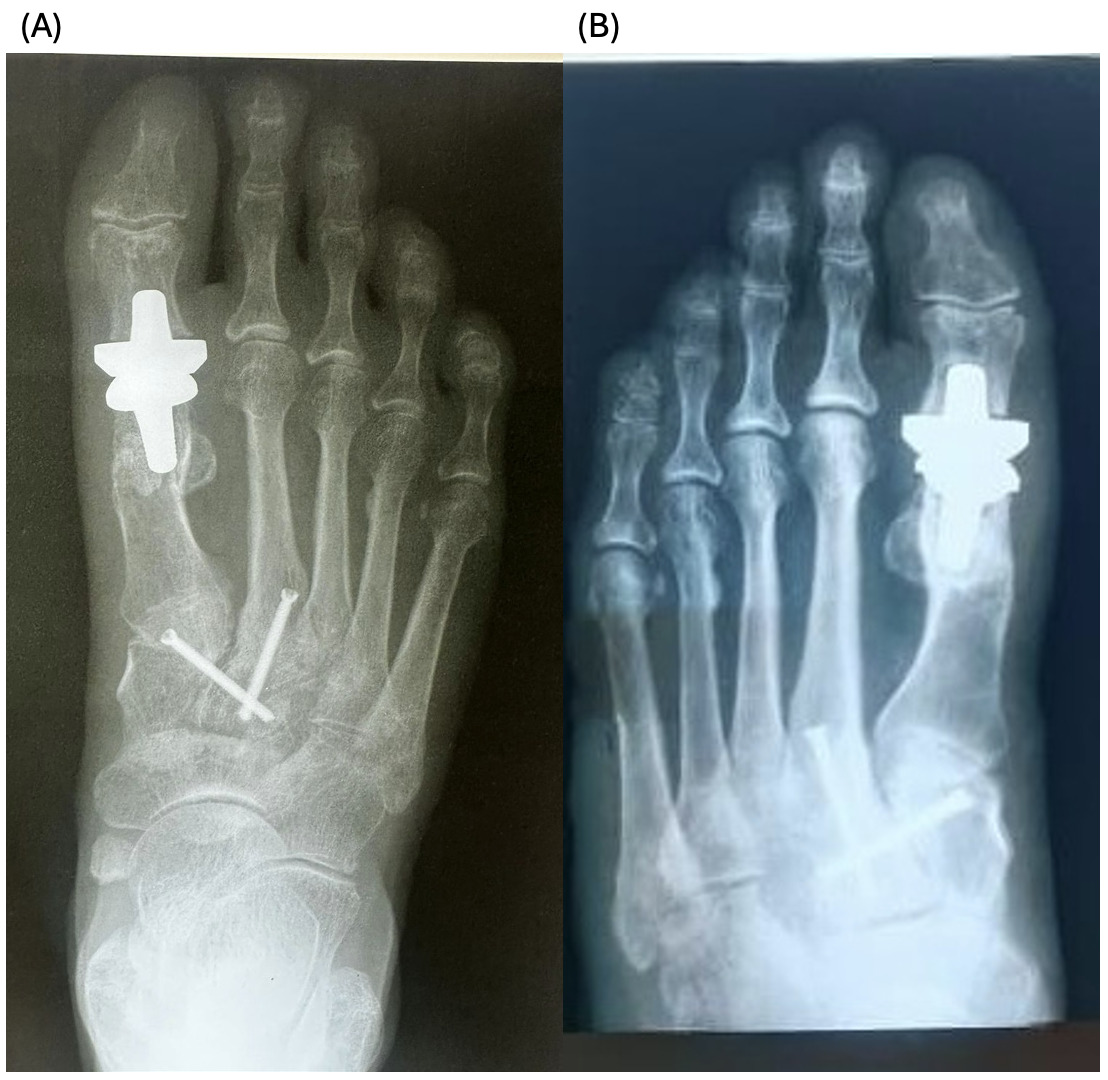

The patients had undergone radiographic evaluation of the MTP joint before the surgery, right after surgery, and 2 and 6 months after surgery (Figures 4-9). The radiographic imaging after the surgery confirmed the correct positioning and alignment. At the follow-up, the radiographic images were done to analyze the early healing process, to observe if there were any signs of implant loosening. 2 months after the surgery, no patient had periprosthetic radiolucencies, no stress-related changes. 6 months after surgery, no osteolysis, no migration of the implant.

This case series demonstrates successful short-term results following total first metatarsophalangeal (MTP) joint replacement using ceramic implants in patients with hallux rigidus. All three patients presented significant improvement in AOFAS scores within 2 months postoperatively, with preserved improvement at 6 months. Notably, Patient C, who had the lowest preoperative score (27/100), achieved the greatest relative improvement, reaching 92/100 at 2 months and 89/100 at 6 months. These functional outcomes were confirmed by physical examination findings, with clear improvements in joint alignment and reduction in deformity (Figure 1-3, (B, C)). Moreover, radiographic imaging revealed no signs of complications such as implant loosening, migration or stress-related changes.